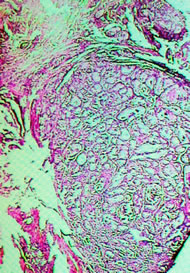

Лекция: "Прогностические факторы при раке предстательной железы".

система градации по Глисону